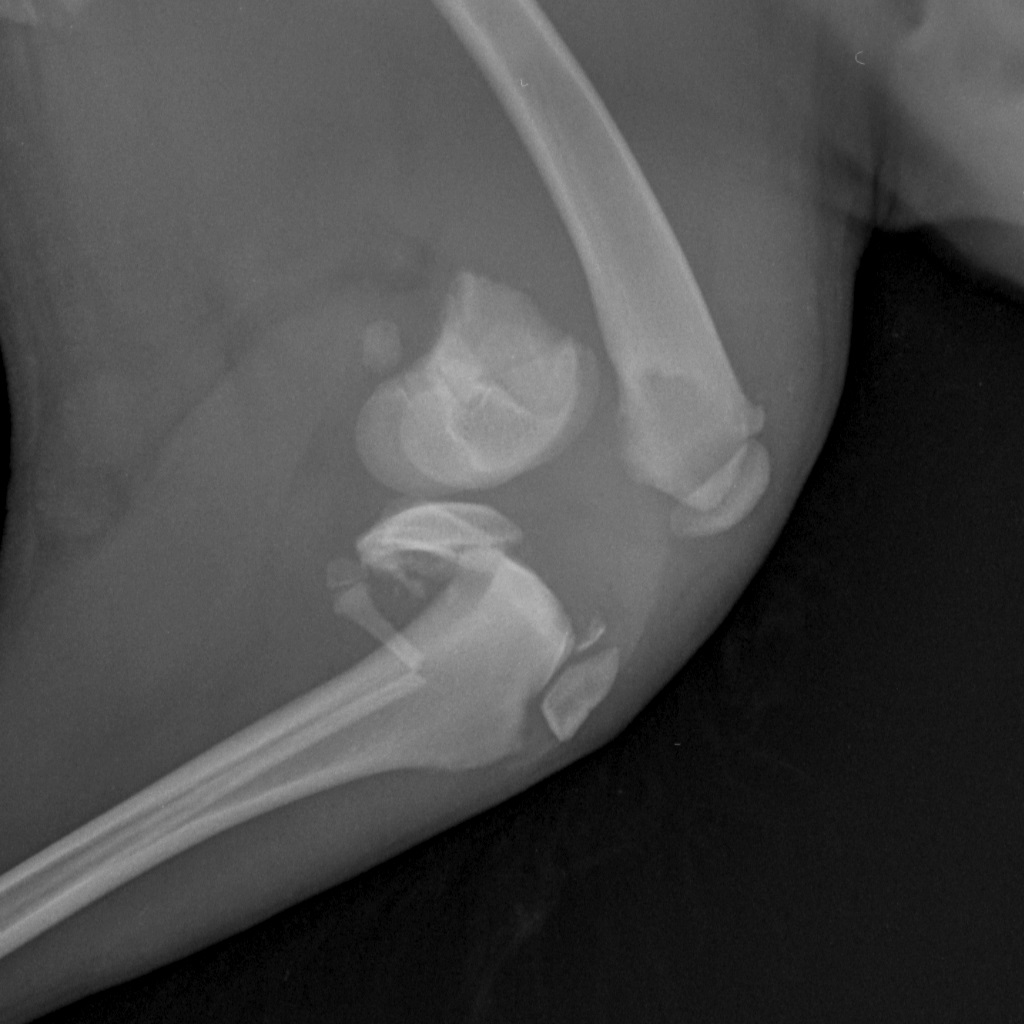

Вот такая бяка у девочки((

Такой мерзкий перелом бывает при прямом ударе по колену

Перелом ужасающий...

Жуть какой перелом! Далекому от медицины человеку - и то смотреть страшно. Впрочем, неудивительно если её из машины на ходу выкинули.

А подсобрать получше эти обломки невозможно, слишком тоненькие косточки?